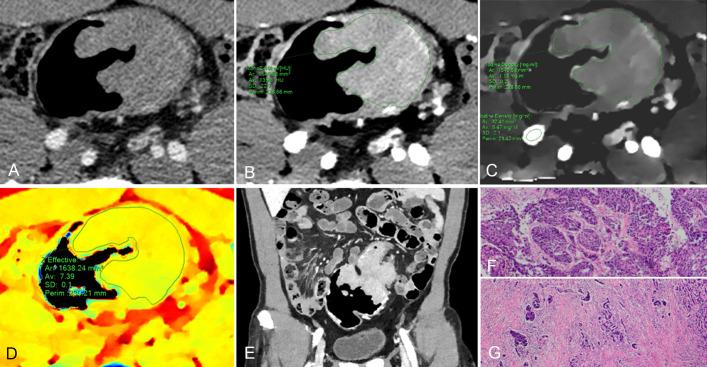

METHODS

A total of 131 patients (mean 62.7 ± 12.9 years; 72 female, 59 male) with pathologically confirmed CRAC (35 pT1-2, 61 pT3, and 35 pT4; 32 high grade and 99 low grade), who received dual-phase DLCT were enrolled in this retrospective study. Normalized iodine concentration (NIC), slope of the spectral HU curve (λHU), and effective atomic number (Eff-Z) were measured for each lesion by two radiologists independently. Intraobserver reliability and interobserver agreement were assessed. The above values were compared between three pT-stage and two histologic-grade groups. The correlation between the pT stages and above values were assessed. Receiver operating characteristic (ROC) curves were calculated to evaluate the diagnostic efficacy.

Intra-class correlation coefficients were ranged from 0.856 to 0.983 for all measurements. Eff-Z [7.21(0.09) vs 7.31 (0.10) vs 7.35 (0.19)], NIC [0.11 (0.05) vs 0.15 (0.08) vs 0.15 (0.08)], NIC [0.27 (0.06) vs 0.34 (0.11) vs 0.35 (0.12)], λHU [1.20 (0.45) vs 1.93 (1.18) vs 2.37 (0.91)], and λHU [2.07 (0.68) vs 2.35 (0.62) vs 3.09 (1.07)] were significantly different among pT stage groups (all <0.001) and exhibited a positive correlation with pT stages (= 0.503, 0.455, 0.394, 0.512, 0.376, respectively, all <0.001). Eff-Z [7.37 (0.10) vs 7.28 (0.08)], NIC[0.20 (0.10) vs 0.13 (0.08)], NIC[0.35 (0.07) vs 0.31 (0.11)], and λHU [2.59 (1.11) vs 1.63 (0.75)] in the high-grade group were markedly higher than those in the low-grade group (all <0.05). For discriminating the advanced- from early-stage CARC, the AUCs of Eff-Z, NIC, NIC, λHU, and λHU were 0.83, 0.80, 0.79, 0.86, and 0.68, respectively (all <0.001). For discriminating the high- from low-grade CARC, the AUCs of Eff-Z, NIC, NIC, and λHU were 0.81, 0.81, 0.64, and 0.81, respectively (all <0.05).